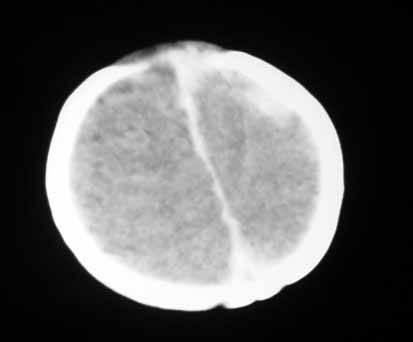

标题: PED0294: 2月婴儿.VitK缺乏症颅内出血.. [打印本页]

标题: PED0294: 2月婴儿.VitK缺乏症颅内出血..

可见 硬膜下及硬膜外血肿,蛛网膜下腔出血

以下是引用jiangjing在2007-8-2 15:07:00的发言:[br]可见 硬膜下及硬膜外血肿,蛛网膜下腔出血

vk缺乏症ct表现有脑实质内出血,珠网膜下腔,硬膜下出血,硬膜外出血,脑实质内出血少见。本病出血要点出血量大,多部位出血,脑室质出血呈团快状。